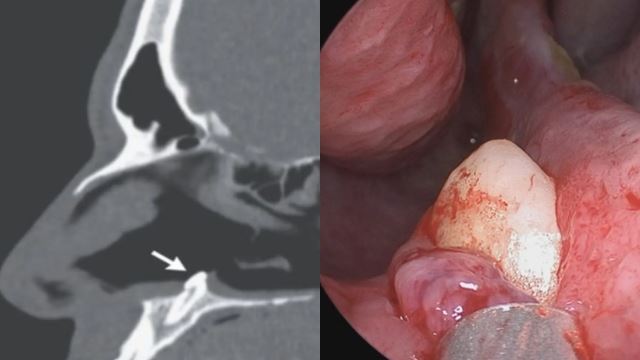

Gigi Tumbuh Dalam Rongga Hidung Ganggu Lelaki Ini Bernafas